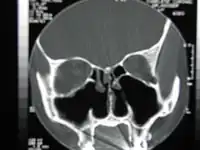

Nez vide après turbinectomie bilatérale totale-CT

La turbinectomie est une intervention chirurgicale destinée à retirer en totalité ou partiellement les cornets du nez. C'est une intervention qui se pratique généralement dans le cabinet d'un oto-rhino-laryngologiste (ORL) à l'aide d'un laser CO2. Elle est recommandée par le praticien lorsque le patient se plaint de gênes respiratoires chroniques.

La turbinectomie peut entrainer le syndrome de nez vide[2].